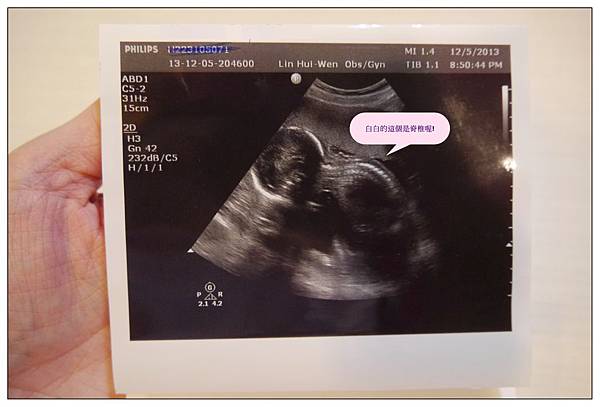

蔡小球的側面照~~~畫面中有一條白色的線那個就是脊椎啦!!!

話說以前我總覺得看別人的超音波照片都看不太懂~~~

原來是要自己當媽了才會看得懂啦~哈